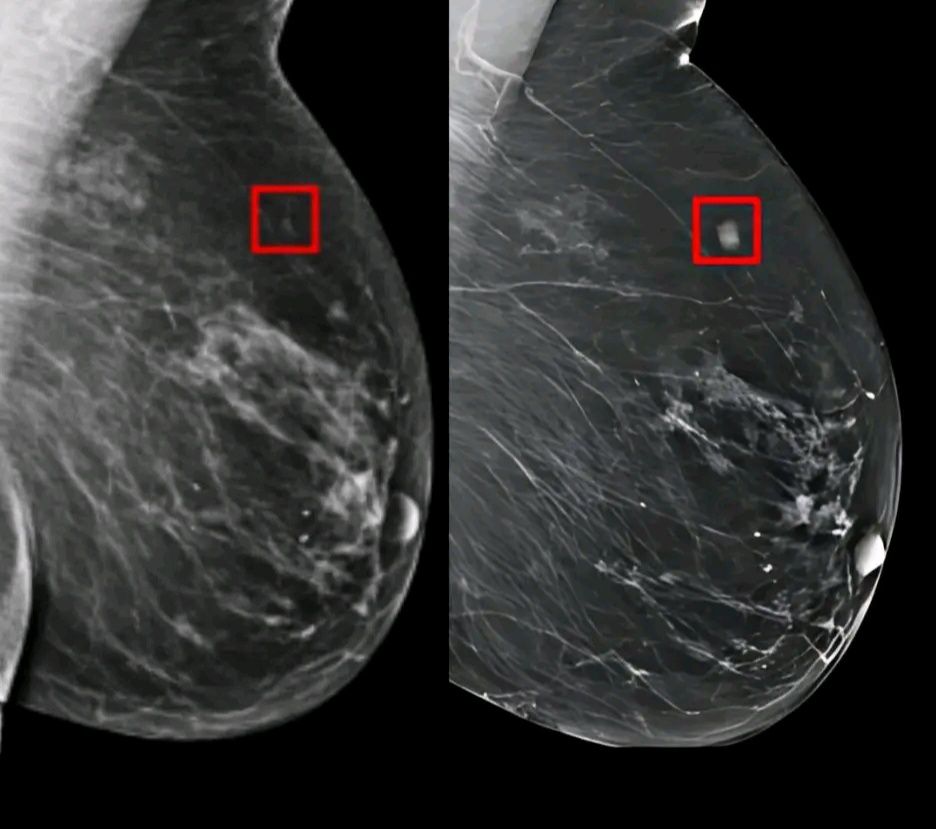

Φανταστείτε να βρείτε καρκίνο πριν καν προλάβει να αναπτυχθεί. Ερευνητές στο Πανεπιστήμιο Duke δημιούργησαν το AsymMirai, ένα AI που αναλύει τις μαστογραφίες με καινοτόμο τρόπο – εντοπίζοντας λεπτές ασυμμετρίες μεταξύ αριστερού και δεξιού στήθους.

Αυτός ο δείκτης που παραβλέπεται αποδείχθηκε ότι είναι ένας ισχυρός προγνωστικός. Σε μια μελέτη πάνω από 210.000 μαστογραφίες, η AsymMirai μπόρεσε να προβλέψει τον κίνδυνο καρκίνου του μαστού έως και πέντε χρόνια νωρίτερα – με ακρίβεια συγκρίσιμη με πιο σύνθετα συστήματα, αλλά πολύ πιο εύκολη για τους γιατρούς.